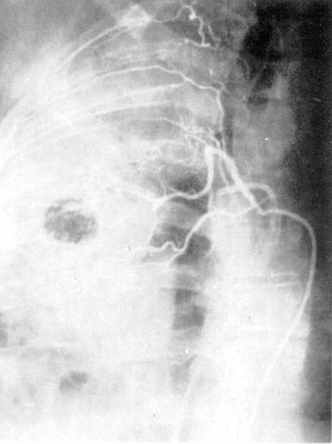

Ангиопульмонография — способ контрастного исследования сосудов малого круга кровообращения. Чаще всего показания к ангиопульмонографии определяются как дифференциально-диагностические: при пороках развития легкого, нагноительных заболеваниях, бластоматозном процессе. Она дает также возможность определить функциональное состояние паренхимы легкого, оценить гемодинамику Различают четыре способа ангиопульмонографии: 1) общую ангиопульмонографию, выполняемую путем внутривенного введения контрастного вещества или посредством ангиокардиографии из правого желудочка сердца; 2) селективную ангиопульмонографию, выполняемую из ствола или ветвей легочной артерии; 3) суперселективную ангиопульмонографию, включающую контрастирование из долевых, сегментарных ветвей легочной артерии; 4) окклюзионную ангиопульмонографию, выполняемую при заклинивании субсегментарной или лобулярной ветви легочной артерии концевой частью сердечного катетера или при блокировании баллоном катетера магистральной ветви легочной артерии. Ангиопульмонография производится в рентгенооперационных, обеспечивающих телевизионный рентгенологический и физиологический контроль, оснащенных автоматическими инъекторами для быстрого, дистанционного и синхронного с рентгенографией введения контрастного вещества (уротраст, верографин и др.) в сосуды и сердце. Сердечный катетер вводится в сосуды, как правило, чрескожно-чрезбедренным способом.

Рис. 6. Ангиопульмонография.

а

— артериальная фаза; б — капиллярная фаза; в — венозная фаза.

Контрастное исследование сосудов средостения включает в себя флебографию и аортографию. Флебография выполняется с учетом характера патологического процесса, выявляемого при помощи рентгенографии, томографии, бронхографии. При указании на вероятное поражение лимфатических узлов переднего средостения выполняют верхнюю кавографию и контрастное исследование внутренних грудных вен, а при подозрении на поражение лимфатических узлов заднего средостения — азигографию. При анализе ангиопульмонограмм обращают внимание на пофазовое продвижение контрастного вещества по различным регионам легкого: легочной артерии, капиллярного русла, венозной системы малого круга кровообращения (рис. 6).

По комбинации ангиографических признаков представляется возможным охарактеризовать вид и распространенность патологического процесса (при двухпроекционной сериографии — посегментарно) в легком, при этом обращается внимание на наличие деформации сосудов, смещение, контуры, разреженность сосудистого рисунка (рарефикацию), степень развития сосудов отдельных сегментов, долей, легкого, характер расположения камер сердца, ротацию сердца и др.